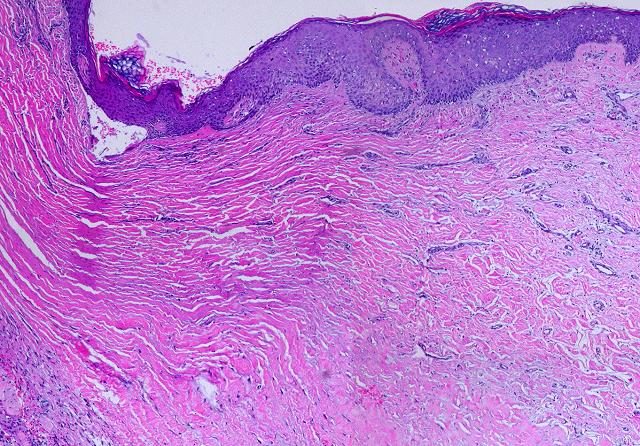

Figure 8

This image is of a single biopsy, taken from a healthy patient with a recent wound which is now covered with typical red granulation tissue. It demonstrates the entire process of normal inflammatory repair, the “wound module”.  Inflammation, which triggers all of the events, always occurs at the surface of a wound.  As time progresses, this creates strata in the wound, new developing layers covering deeper older levels which first evolved so many days ago.  Timewise sequential biopsies are not needed to tell the story of inflammatory repair, because looking deeper into a fully proliferated wound is to see its entire history.  The whole specimen, shown on the left, is about 6-8 millimeters thick.  The right side has 8 high resolution views of the various strata.

Level 1, the inflammatory zone.  The wound is capped by a shell of eosinophilic fibrin and plasma.  It is heavily infiltrated with blood borne acute inflammatory cells (neutrophils, lymphocytes, monocytes).  Absent an epidermis, this inflammatory layer sequesters and protects the underlying host.  Platelets and leukocytes are releasing cytokines which are inducing the transformation of monocytes to macrophages, seen as occasional enlarged mononuclear cells. (The onset and evolution of this event, from the time of acute injury, is typically several hours to 2 or 3 days; typical times for other events are given below.)

Level 2, the macrophage zone.  Transformed macrophages are large, interspersed with a lower concentration of other inflammatory cells.  Some eosinophilic plasma and hemorrhage from underlying new vessels has stained this specimen, but it is the pale basophilic areas which are characteristic.  This pale zone is filled with mucoid glycosaminoglycans, the viscous ground substance in which cells can survive and migrate.  There are no fibroblasts nor connective proteins nor any organized cellular structure, so this aminoglycan “ether” is the entire universe to cells at this level.  These GAG’s, which are made by inflammatory and transformed cells, have a different composition and structure than those in the Integra matrix, and thus different effects on cells.  Macrophages at this level have the keystone role of making pro-proliferative cytokines which will transform and attract histogenetic cells from underlying blood vessels.  (1 to 4 days.)

Level 3, angioblast streaming.  In this zone, stimulated angioblasts which have arisen from deeper source vessels, are streaming toward the macrophages making angiogenic factors.  They are long migratory spindle cells moving through the aminoglycan ground substance.  They are surrounded by inflammatory cells migrating to the inflammatory zone penthouse.  As angioblastic cells reach this area, they start to reform tubular vessels.  (3 to 5 days for onset.)

Level 4, vessel organization zone.  Angiocytes have reformed tubular vessels and are now conducting blood.  This provides crucial circulation and logistical support to the wound, creating the necessary conditions for the other major cell line, the fibroblasts, to begin functioning.  Numerous neutrophils can still be seen, mostly around the new vessels, because this is where they must exit to make their way to the top.  However, a few young round fibroblasts can be seen, and some faint pink eosinophilia attests to the beginnings of some connective protein formation.  (4 to 7 days.)

Level 5, non-inflammatory transition zone.  At this level, the incipient tissue is fully sequestered from inflammatory stimuli.  There are no inflammatory cells (except a few in-transit neutrophils).  Small round cells between vessels are young fibroblasts.  There is not yet much structure to the pink collagen, but it is getting more noticeable.  (5 to 10 days).

Level 6, fibroblast accumulation zone.  The space between vessels is filled with young round histogenetic cells.  They are poorly organized, but some clustering and orientation is evident.  Collagen is showing some organization and fibrous structure.  This is the first level at which things are becoming more “tissue” than “granulation”.  (7 to 12 days.)

Level 7, fibroblast maturation zone.  Inflammatory cells have long since disappeared from the picture.  There are nearby large conducting blood vessels supplying the proliferating capillaries above.  Fibroblasts are becoming flattened, oriented, clustered, and entrapped in the collagen they are making, looking now like classic fibroblasts.  The new fibrous tissue is about 50% cells, 50% collagen.  (7 to 15 days.)

Level 8, fibrous consolidation zone.  Fibrous scar is becoming organized.  The tissue is more protein than cell.  Collagen is forming long thick bundles, and tensile strength is developing.  Usually present at 10 to 20 days, dense consolidation is barely yet occurring in this particular specimen which was taken only 10 days after injury.  As time continues, this collagen will become clinical scar, thicker, denser, and more non-compliant (figure 11).